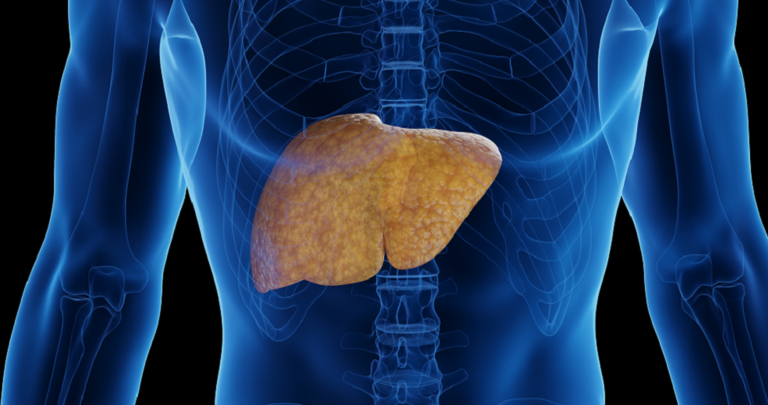

تحذير هام لمرضى الكبد من غذاء شائع

وجدت تجربة سريرية صغيرة في الولايات المتحدة أن الحد من تناول اللحوم يقلل من تراكم غاز الأمونيا الضار لدى المصابين بمرض الكبد في مراحله المتأخرة.

وتعتبر الأطعمة الغنية بالبروتين، خاصة من مصادر حيوانية، جزءا من نظام غذائي صحي، لكن الدراسة الجديدة تكشف أن الاعتدال في تناول اللحوم قد يخفف العبء على الأشخاص المصابين بتليف الكبد.

وأوضح الباحثون أنه كلما زاد استهلاك اللحوم، زادت كمية الأمونيا التي يتعين على الكبد معالجتها، وسيواجه الكبد التالف بالفعل صعوبة في إنجاز المهمة، ما يؤدي إلى تراكم الأمونيا في الدم، وهو ما يرتبط بالاعتلال الدماغي الكبدي (HE نوع من التدهور المعرفي).